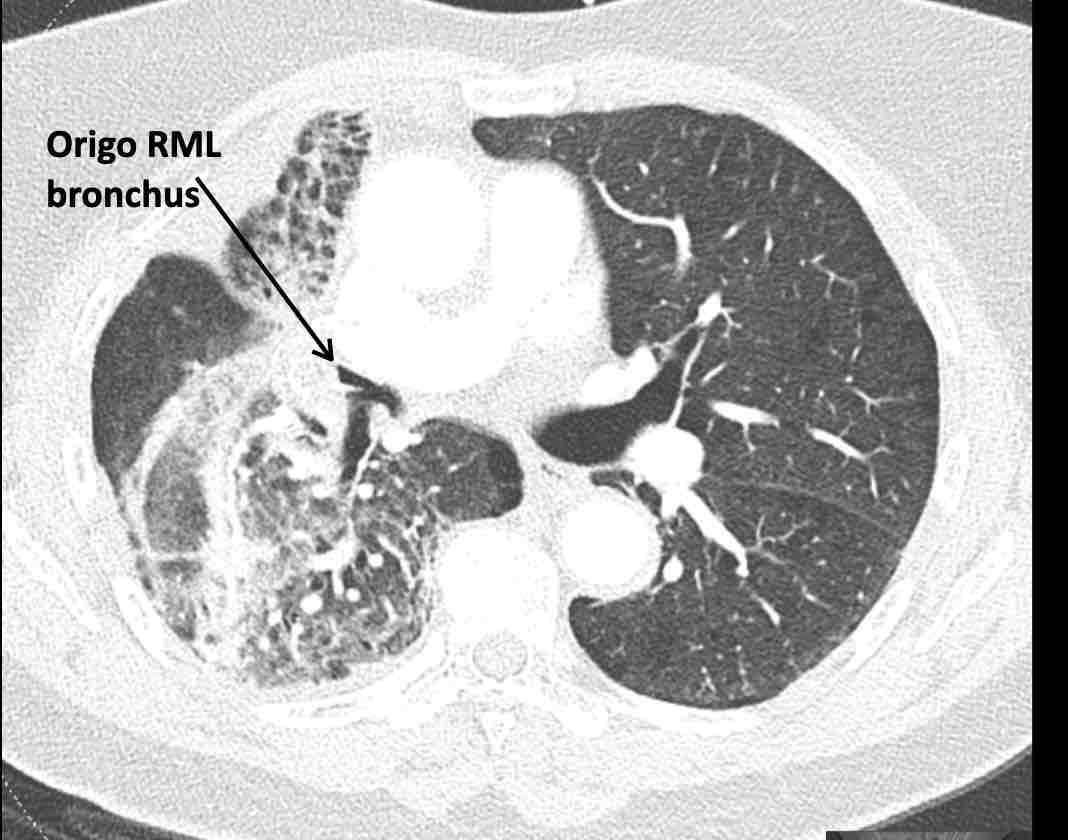

Những thay đổi cấu trúc lan rộng ở nửa ngực phải sau hóa xạ trị cho ung thư phổi không tế bào nhỏ (NSCLC) giai đoạn 4.

Theo dõi đường đi của các phế quản cho thấy thùy trên phổi phải phần lớn còn thông khí, trong khi